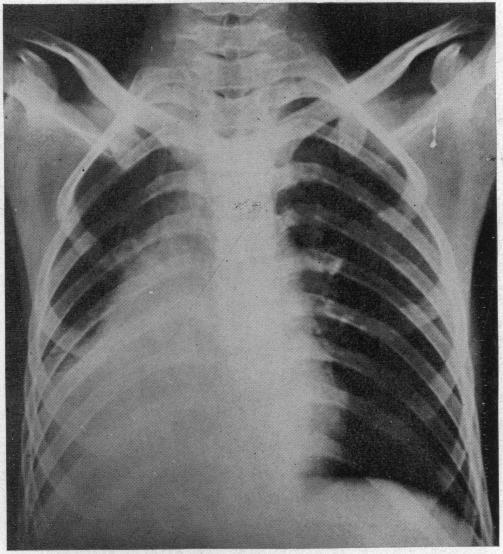

ACUTE MASSIVE COLLAPSE OF THE LUNGS: A DISCUSSION OF ITS MECHANISM AND OF ITS RELATION TO FOREIGN BODIES IN THE BRONCHI AND POST-OPERATIVE COMPLICATIONS.

Ann Surg. 1925 Sep;82(3):364-89. doi: 10.1097/00000658-192509010-00005.